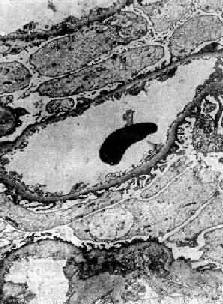

光学显微镜下,肾小球无明显变化或仅有轻度节段性系膜增生。电镜下见弥漫性肾小球脏层上皮细胞足突消失(图12-20),细胞内高尔基器和内质网增多,并可见脂滴。细胞表面常有多数微绒毛形成。足突消失不仅见于脂性肾病,也常见于其他原因引起的大量蛋白尿和肾病综合征。经过治疗或蛋白尿等症状缓解后,脏层上皮细胞的变化可恢复正常。

图12-20 轻微病变性肾小球肾炎

电镜下见肾小球毛细血管上皮细胞部分足突消失